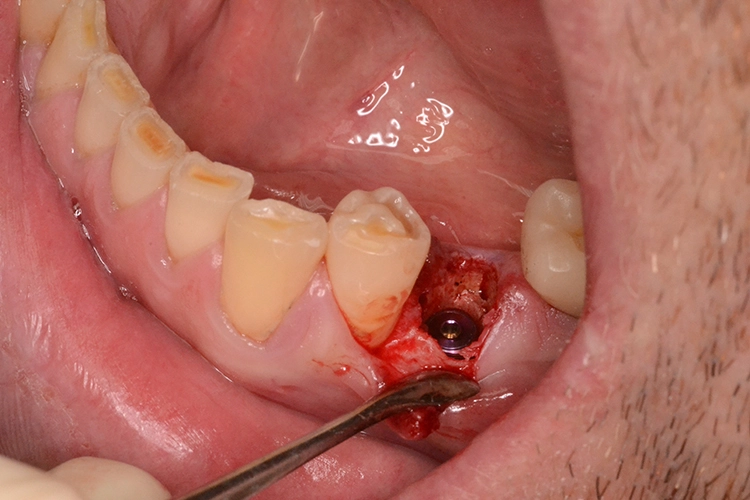

Im präoperativ angefertigten DVT (Abb. 3b und c) zeigte sich um die Wurzelspitze ein chronisches Entzündungsgeschehen, welches die vestibuläre Lamelle im apikalen Wurzelbereich des Zahnes 23 komplett aufgelöst hat. Da jedoch der Bereich direkt apikal von 23 nicht vom Geschehen betroffen war, fiel die Entscheidung zur Sofortimplantation auch, da der Patient blutverdünnende Medikamente einnehmen musste, welche durch Kombination von Extraktion und Implantation nur einmal abgesetzt werden mussten. In diesem Fall war aufgrund des Knochendefektes die Bildung eines Volllappens mit Entlastung unumgänglich.